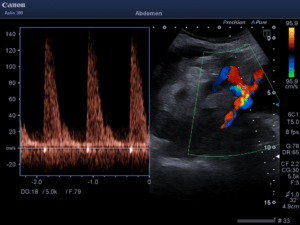

As a safety measure for IJ vein cannulation, guidewire visualization in the proper target vessel prior to dilation seems intuitively beneficial. This technique, however, may not be foolproof. At least one author has reported carotid artery cannulation despite prior wire confirmation in the IJ vein [17]. The needle, and subsequently, the wire was thought to have traversed the lumen of the vein en route to a more posteriorly located artery. Others have reported inadvertent cannulation of the subclavian artery after guidewire visualization in the IJ vein [18, 19]. It appears that how the vessels and wire are scanned is relevant.  In one of the above cited cases of subclavian artery cannulation, the operator was unable to obtain a longitudinal (in-plane) view of the wire due to its proximity of the clavicle [18]. We concur with other authors that a longitudinal view of the guidewire is important to obtain [20]. Such a view permits the operator to observe the course of the wire over several centimeters as it passes into the lumen of the vessel and continues distally. Figure 1 demonstrates this longitudinal approach with the guidewire placed in the carotid artery of the vascular access model used in our study. Figure 2 shows the wire in the same vessel in a transverse (out-of-plane) view. When using the latter approach, the wire should be visualized within the IJ vein and followed along its course to ensure that it does not proceed distally through the posterior wall of the target vessel and into the carotid artery. In our experience, obtaining both longitudinal and transverse views takes little additional time and may confer additional certainty of the wire’s position.

Figure 1. Longitudinal (in-plane) view of the guidewire (arrow) coursing through the carotid artery in an inanimate vascular access model.

Figure 2: Transverse (out-of-plane) view of the guidewire (arrow) coursing through the carotid artery in an inanimate vascular access model. Note that no guidewire is demonstrated in the internal jugular (IJ) vein at right.